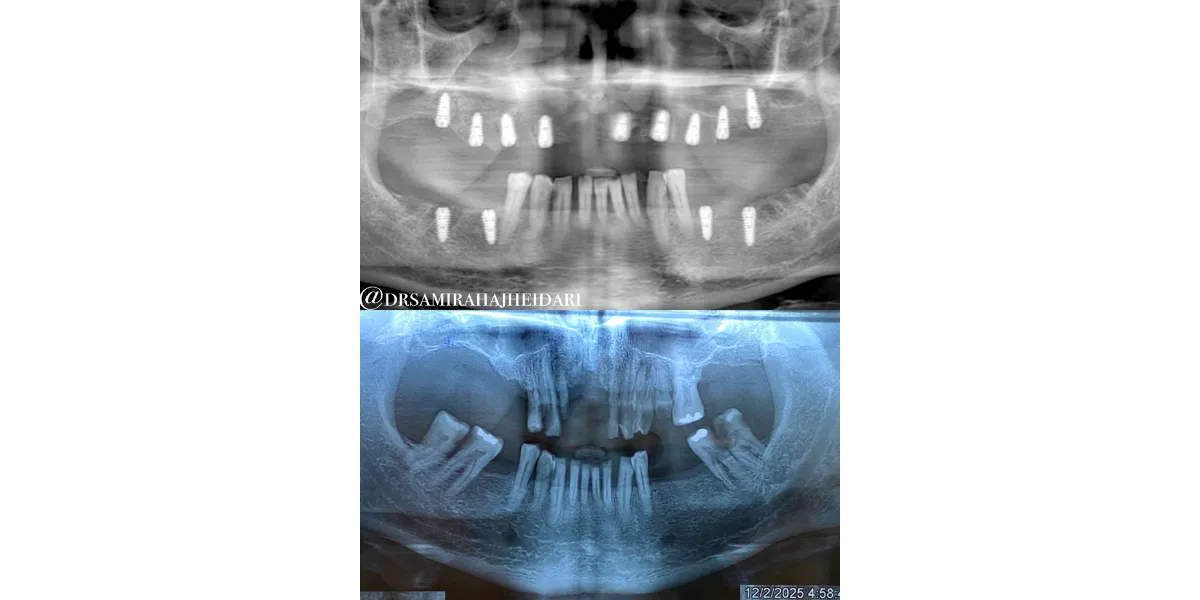

ترکیب اسکن داخل دهانی با عکس رادیولوژی ایمپلنت دندان

در روشهای دیجیتال، اطلاعات اسکن داخل دهانی با عکس رادیولوژی ایمپلنت دندان (مانند CBCT) ترکیب میشود. این ترکیب باعث میشود:

- وضعیت استخوان فک دقیق بررسی شود

- محل عصبها مشخص شود

- ضخامت استخوان ارزیابی گردد

- بهترین محل برای کاشت تعیین شود

در نهایت، با استفاده از این دادهها یک گاید جراحی طراحی میشود که محل دقیق کاشت ایمپلنت را مشخص میکند.